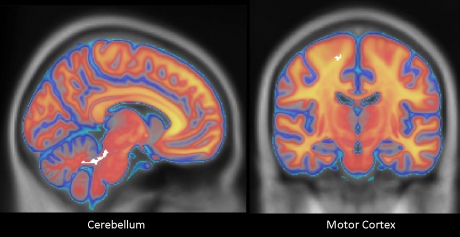

不过,罗伯茨也发现,空手道选手空有肌肉也不代表能打出有力的重拳。相反,当罗伯茨运用运动追踪摄像机来观察出拳者关节的运动,发现那些像李小龙一样把身体各处运动的加速峰值集中在一起出击的人,能打出最有力的一拳。而在对受试者的脑部进行扫描后,罗伯茨发现,受试者进行2英寸出拳的力量与协调性与他们大脑辅助运动皮层中白质的微结构差异直接相关。白质负责管控脑细胞之间的交流。

罗伯茨发现两组受试者与运动控制的脑部区域(白色部分)的白质存在显著差异。图片来源:imperial.ac.uk  Z! P, y$ Z( g& K

由于运动辅助区负责协调肢体肌肉,而近距离出拳依赖于这种协调性,所以这些发现相当重要。罗伯茨说,白质的改变能够允许这部分大脑区域得以具备更丰富、更复杂的脑细胞连接,这可能会增加出拳者校准动作的能力。